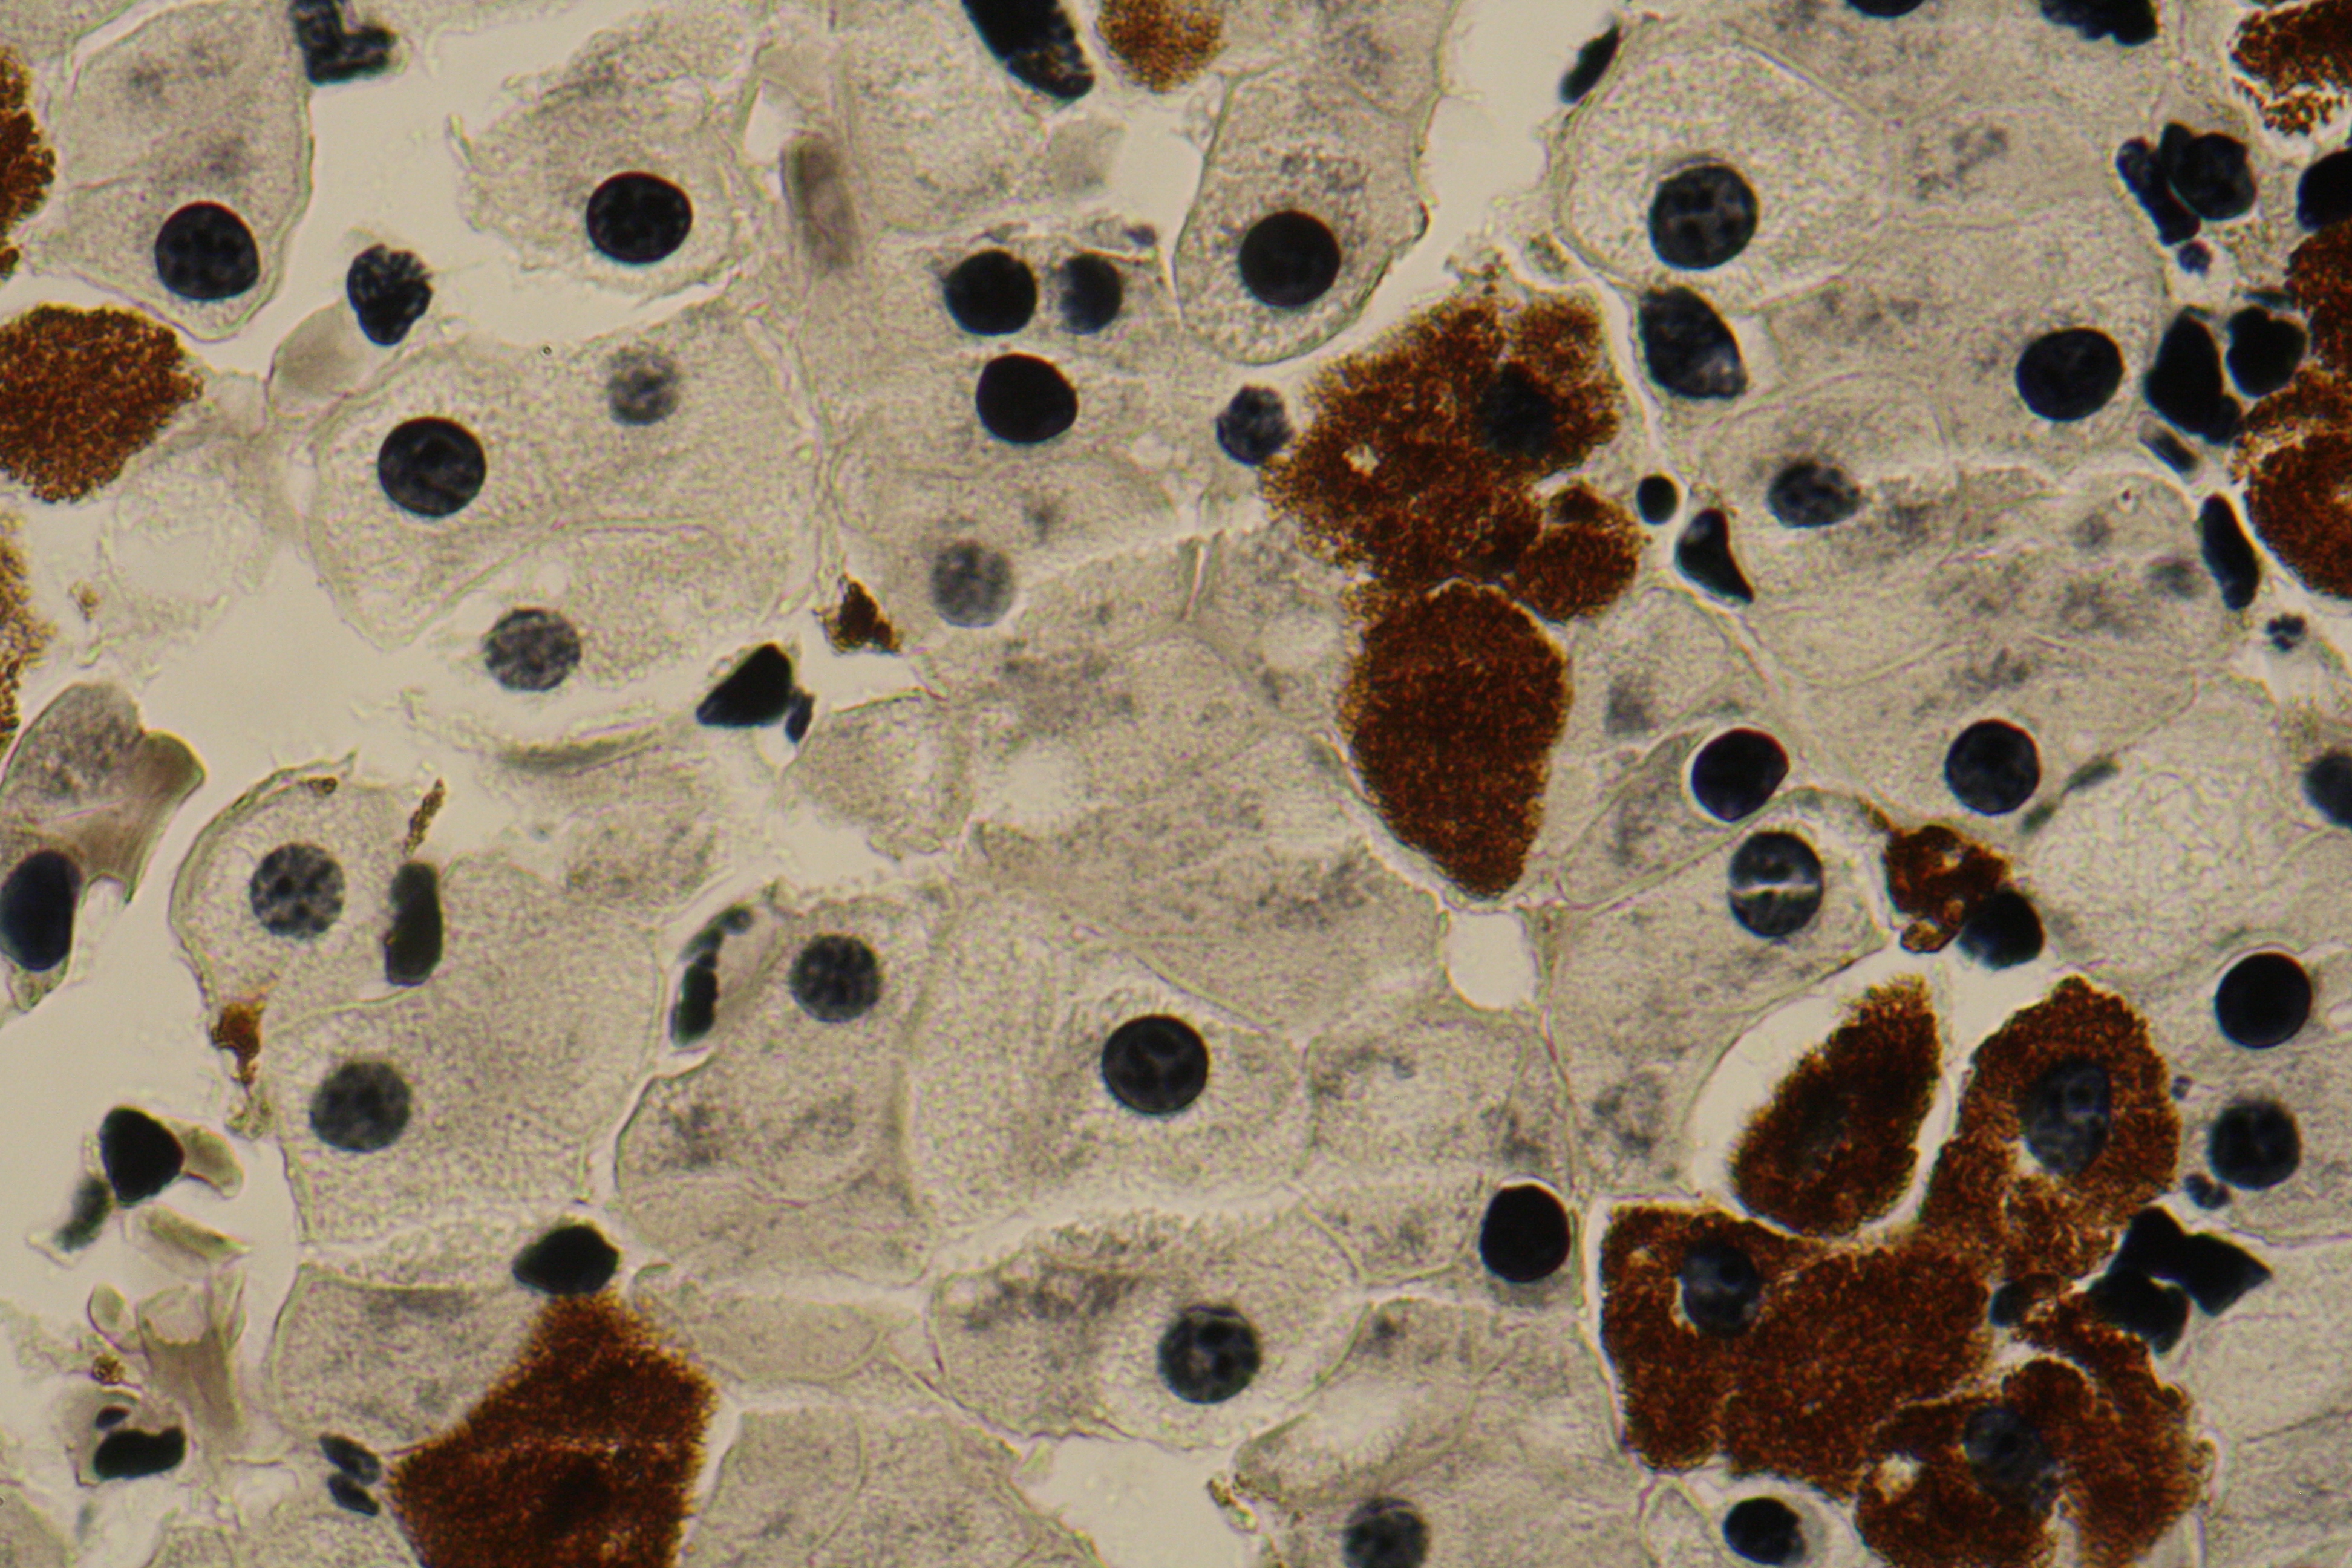

Liver with Kupffer cells

Liver with macrophages – kuppfer cells